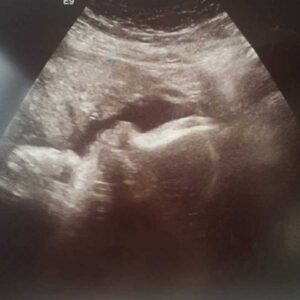

Twenty weeks came quick, even though at the time I felt like I’d never find out if the baby was a girl or boy. At that doctor’s appointment, the baby’s dad, my mom and dad all filled a tiny room. We had to bribe the nurse to let us all in, but I couldn’t imagine finding out such information alone. The ultrasound jelly was cold on my belly, then I saw my baby flash on the screen. There my little love was, dancing around with such a strong heartbeat. The ultrasound technician did her measurements quietly while we ooo-ed and ahh-ed. She asked if we wanted to know the sex of the baby, but I had already seen on the screen.

To keep an eye on Jensen, I had two ultrasounds a week. It was an hour drive to and from there, but seeing him grow and move on the screen gave me so much joy. I’ll never regret all the time I spent in that doctor’s office. Hearing Jensen’s heartbeat and seeing him was my peace during my pregnancy.

At my 38-week appointment, I found out Jensen had died. The screen wasn’t dancing as it usually did. Jensen was just slumped there. His heart wasn’t flickering, everything was just… still.